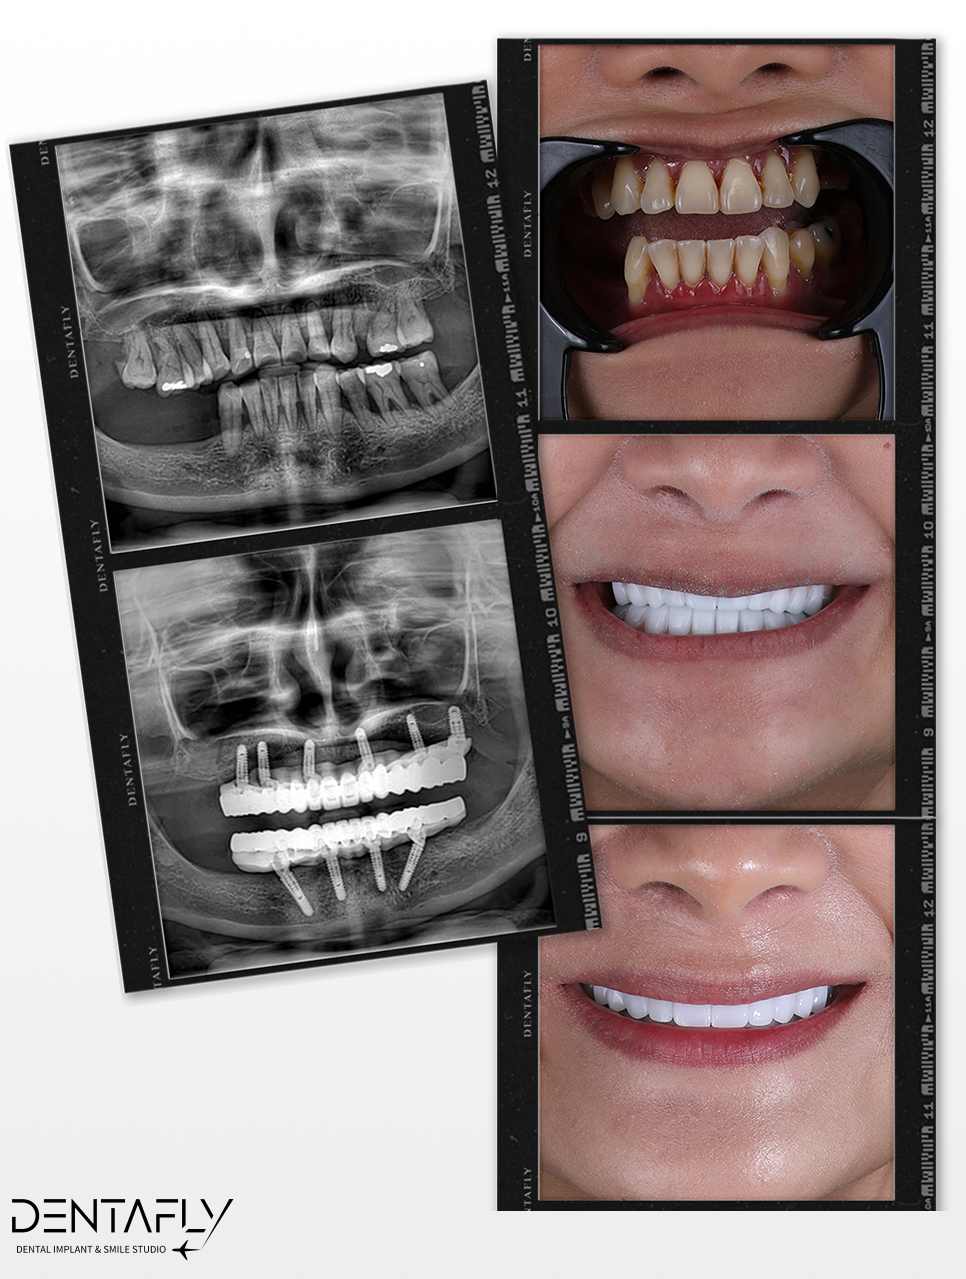

Witness the Transformation: All on 6 Before & After

A permanent full-arch restoration is a masterclass in surgical precision and prosthetic design. Explore our gallery to see how the All on 6 protocol translates into real-world transformations for UK patients—natural finish, restored facial volume, and harmonious smiles.